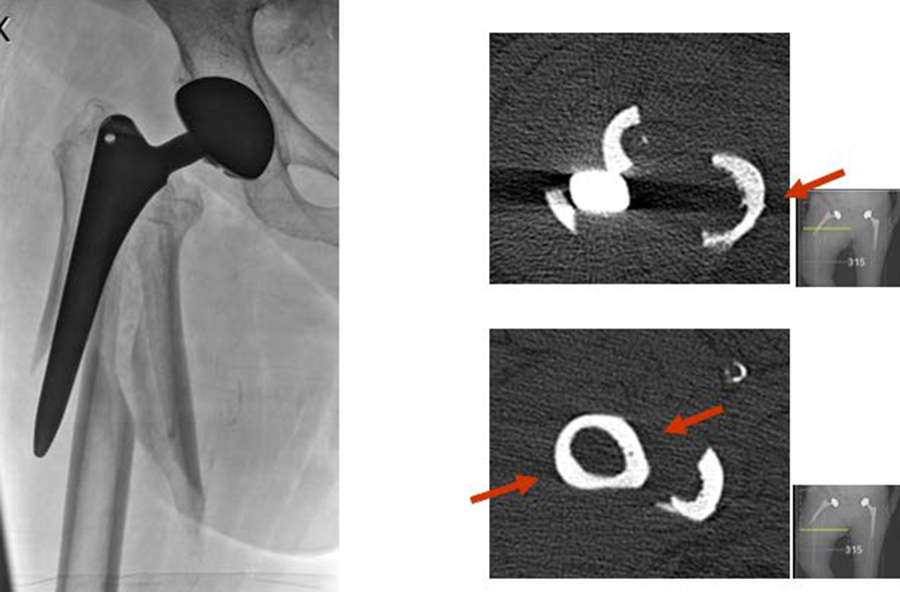

Assessing the stem

As has been discussed in Part 2 of this series, one essential diagnosis in treating PPFF is to determine whether a stem is loose. This question often translates into, "Is the fracture Vancouver type B1 or type B2/B3?" To achieve a reasonably accurate diagnosis, it is essential to take high-quality x-rays in at least two planes at the pelvis level to determine if the stem is loose or stable. Radiolucent lines detected around the prosthesis or cement is an indication of osteolysis, stem loosening, or stem subsidence [1]. A computed tomographic (CT) scan is helpful in showing fracture pattern, extension of osteolysis, and even implant fixation. If the imaging does not offer a conclusive diagnosis of a stable stem, and during surgery implant stability is still doubtful, then a stem revision should be carried out.